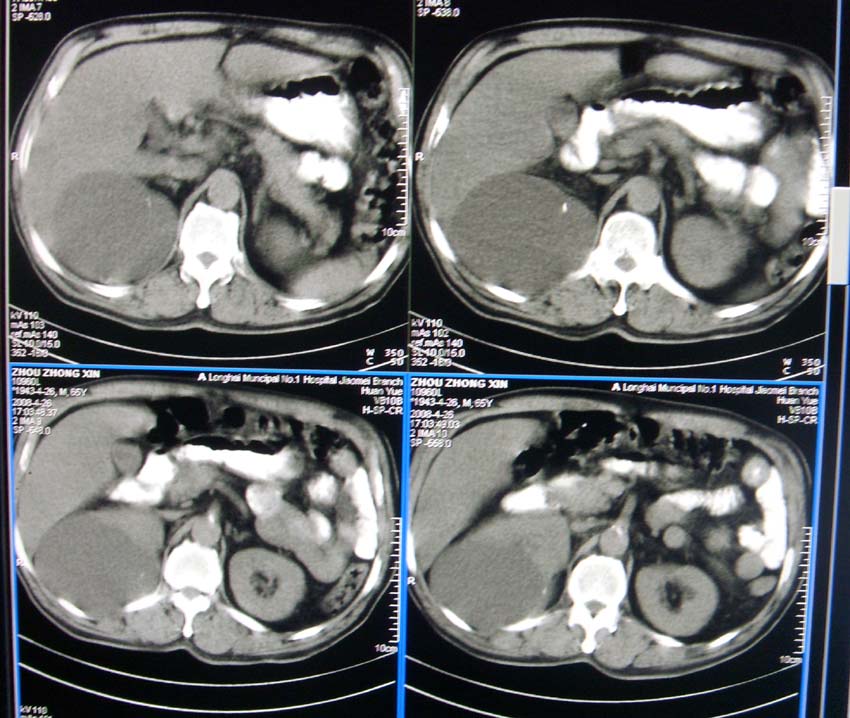

以下是引用liangshusheng在2008-4-27 13:28:00的发言:[br]双肾都有结石,右肾积水波浪状,输尿管积水,建议往下扫

以下是引用zjzjr在2008-4-27 14:25:00的发言:[br]1,右侧多发囊性占位,考虑囊肿可能大。[br]2,肾下部输尿管走行区囊性占位,巨输尿管?建议mru。